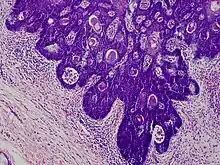

Folliculosebaceous cystic hamartoma

Folliculosebaceous cystic hamartoma abbreviated as (FSCH) is a rare cutaneous hamartoma consisting of dilated folliculosebaceous units invested in mesenchymal elements.[1]:676 it typically affects adults, have a predilection for the central face or scalp, with less than 1.5 cm dimension.[2] Clinically, the lesions are asymptomatic, rubbery to firm in consistency, and usually occur on or above the neck in (> 90%) of cases, Histopathologically, FSCH shares several similar features to sebaceous trichofolliculoma, but it is usually possible to differentiate these two tumors.[3]